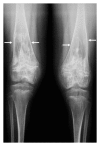

Figures